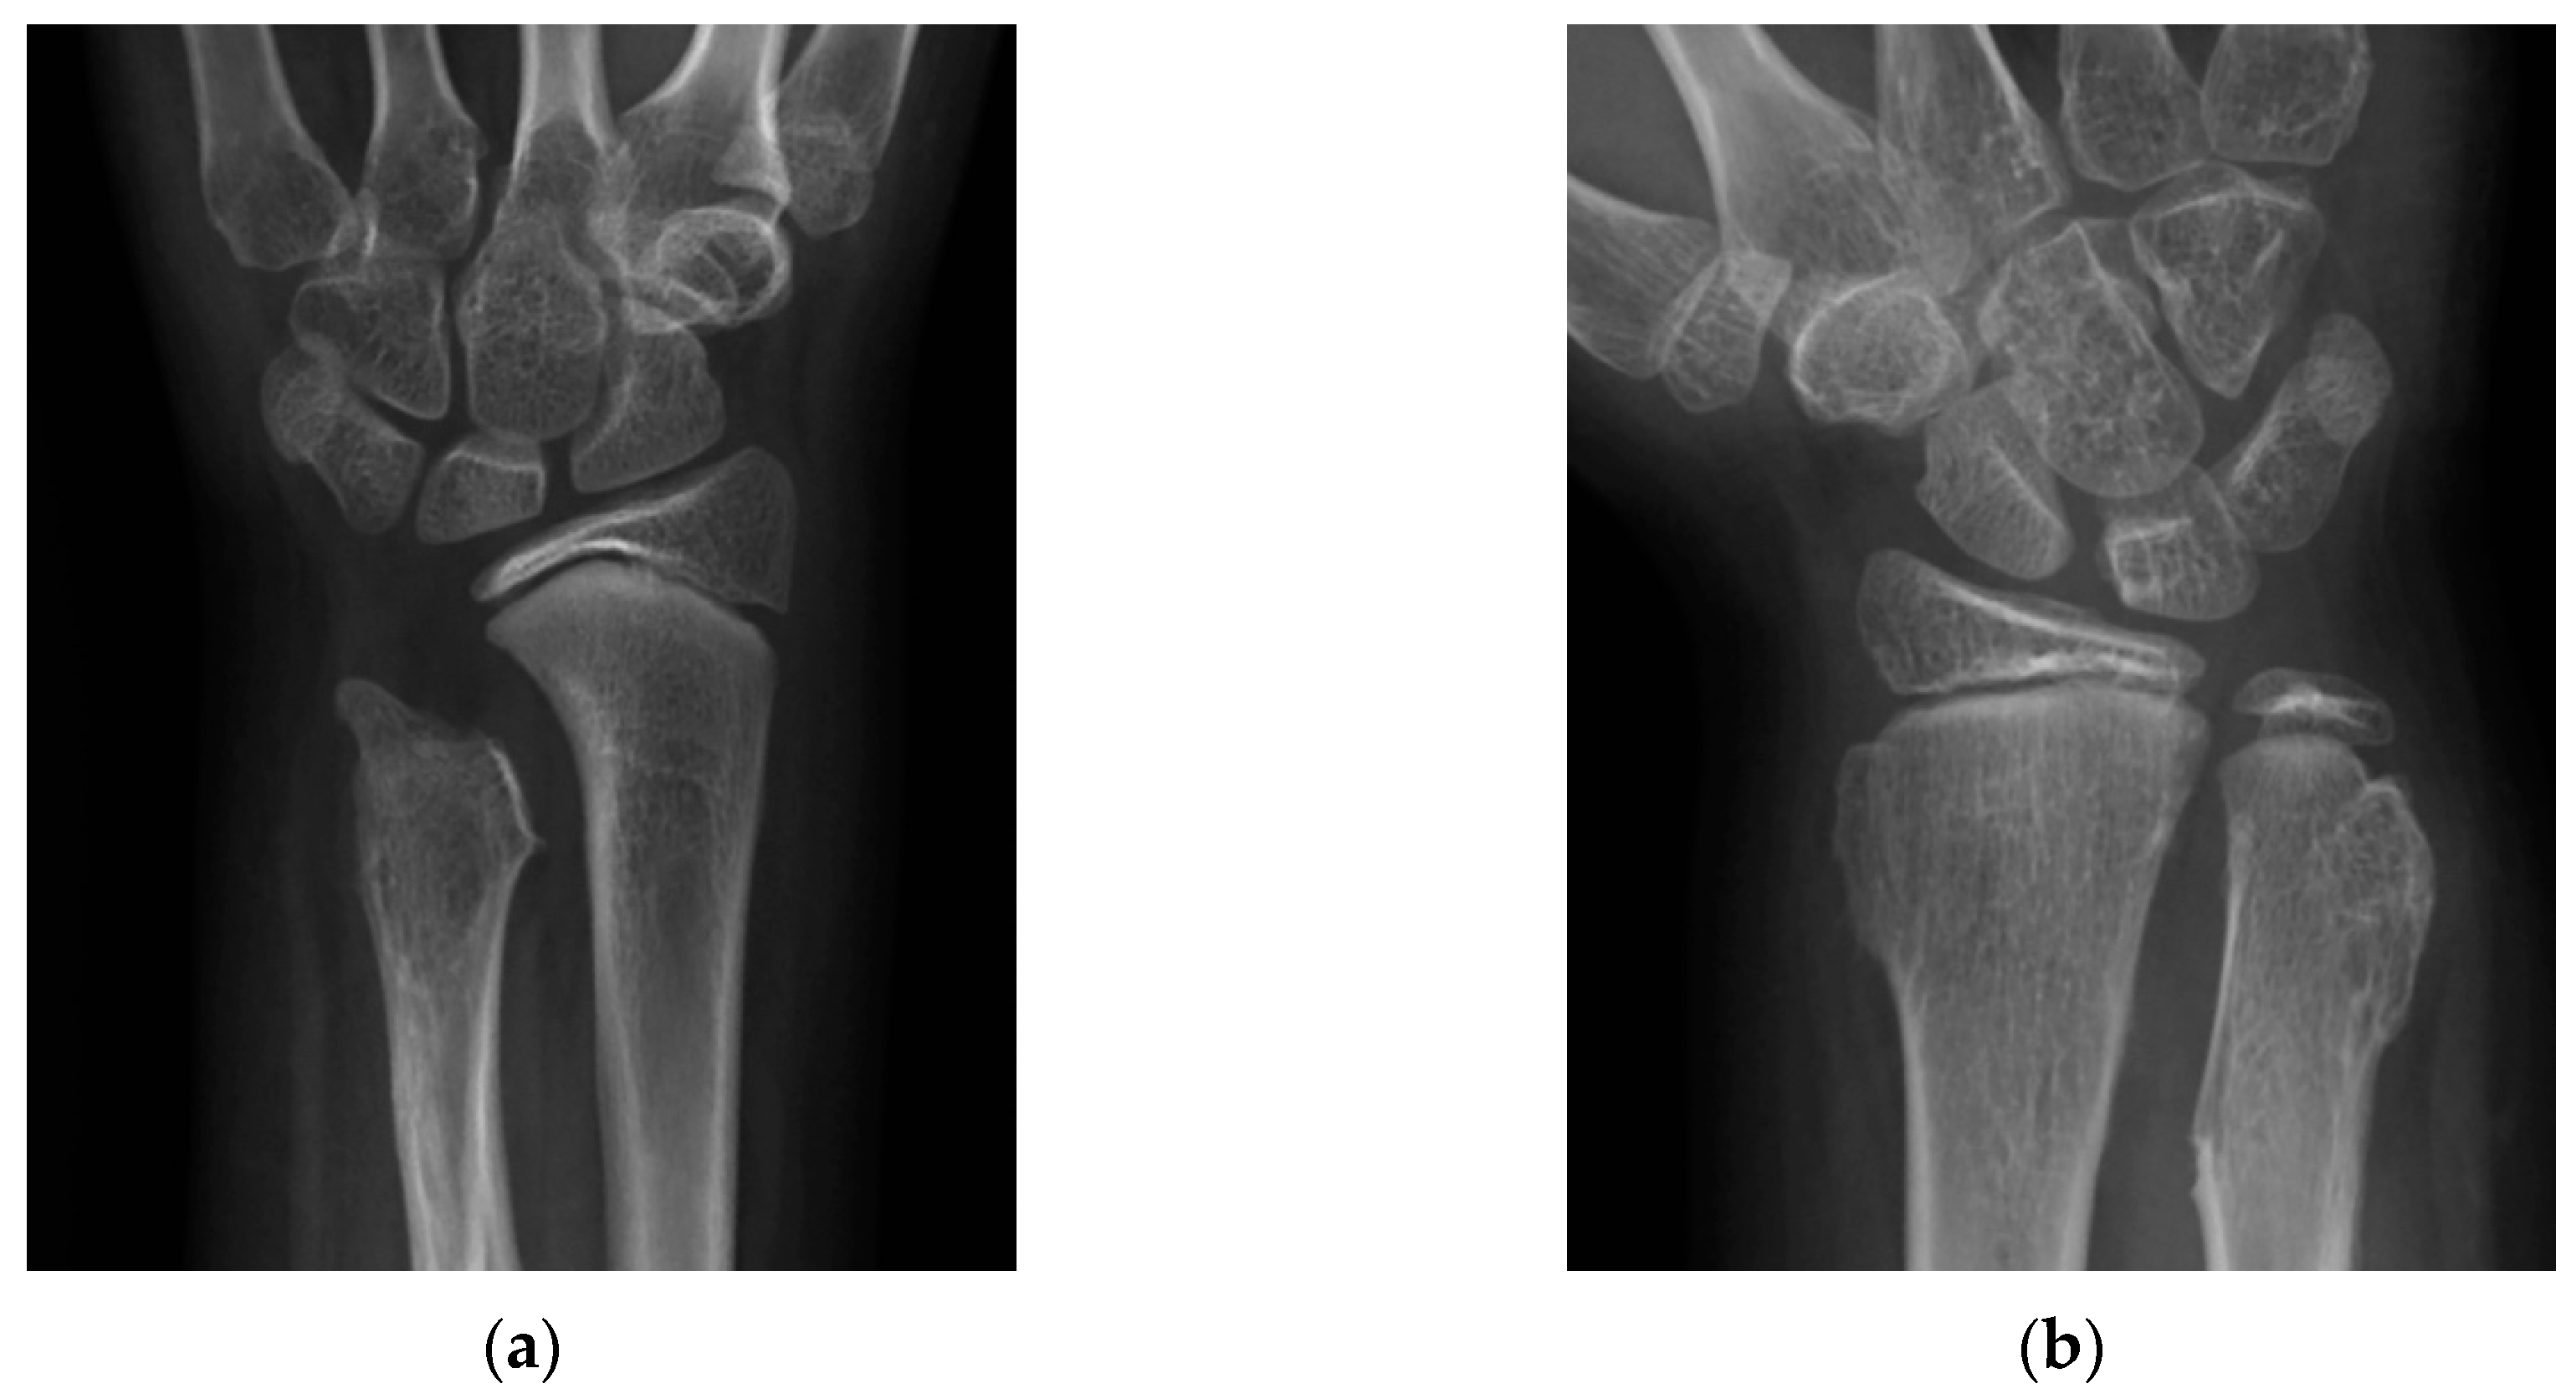

| UV (mm) | |||

| Preoperative | −16.8 ± 2.9 | −14.5 ± 2.4 | 0.11 |

| Follow-up | −0.2 ± 3.2 | −4.6 ± 7.0 | 0.32 |

| RAA (°) | |||

| Preoperative | 35.8 ± 5.2 | 38.8 ± 2.5 | 0.44 |

| Follow-up | 22.9 ± 4.7 | 31.2 ± 7.7 | 0.07 |

| CS (%) | |||

| Preoperative | 46.7 ± 11.0 | 60.8 ± 12.3 | 0.11 |

| Follow-up | 31.3 ± 7.6 | 47.4 ± 3.6 | 0.01 |